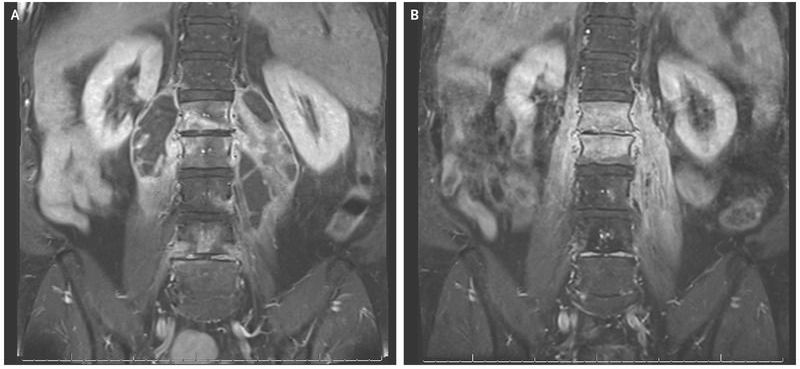

A 62-year-old man presented to the emergency department with a 6-month history of worsening low back pain, fevers, chills, night sweats, and weight loss. He regularly traveled to Mexico and had occasionally consumed unprocessed dairy products. He had no history of tuberculosis infection or known exposure. Laboratory studies revealed a white-cell count of 10,600 per cubic millimeter (reference range, 3700 to 10,500) and an erythrocyte sedimentation rate of 65 mm per hour (reference range, 0 to 15). Magnetic resonance imaging (MRI) of the lumbar spine with the use of gadolinium enhancement revealed findings consistent with spondylitis of the first through fifth lumbar vertebrae, as well as large psoas abscesses with multiple loculations (Panel A). Cultures from the blood and a psoas abscess grew Brucella melitensis; a mycobacterial culture was negative. B. melitensis is transmitted to humans from goats and sheep, typically through the consumption of unpasteurized dairy products in countries where this bacterium is endemic. A drain was placed, and the patient was treated with doxycycline with rifampin for 5 months. A repeat MRI scan obtained 3 months after the completion of treatment showed reduction of the psoas abscesses but continued enhancement of the first and second lumbar vertebrae (Panel B). The patient’s fever, night sweats, and low back pain resolved, the levels of inflammatory markers declined, and he remained symptom-free at follow-up 2 years later.